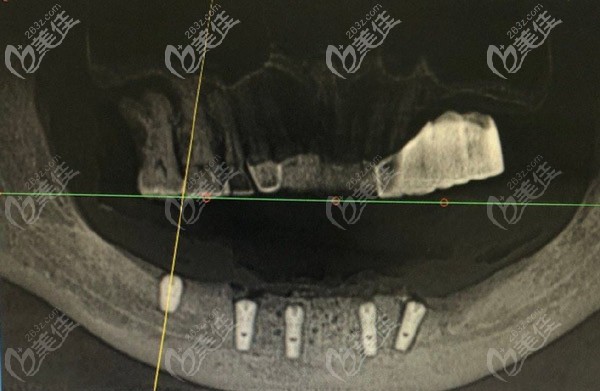

VIIV缺骨種植技術(shù)的原理:

突破了傳統(tǒng)種植牙對(duì)牙槽骨條件的限制,顧客不需要植骨,不用在等長(zhǎng)達(dá)一年的時(shí)間,就可以種牙。

采用的是哪里有骨哪里種,通過(guò)不同角度種植的方式,只需要4-6顆種植體就能恢復(fù)半口牙,避免多次手術(shù)的創(chuàng)傷。www.xqnp.cn

即刻種植:4-6顆植體恢復(fù)半口牙,當(dāng)天種牙當(dāng)天吃美食。

缺骨種牙:無(wú)需植骨,避免骨粉、骨膜費(fèi)用及植骨費(fèi)用。

適應(yīng)癥廣:牙槽骨萎縮、骨質(zhì)疏松、無(wú)牙頜也能輕松種牙。